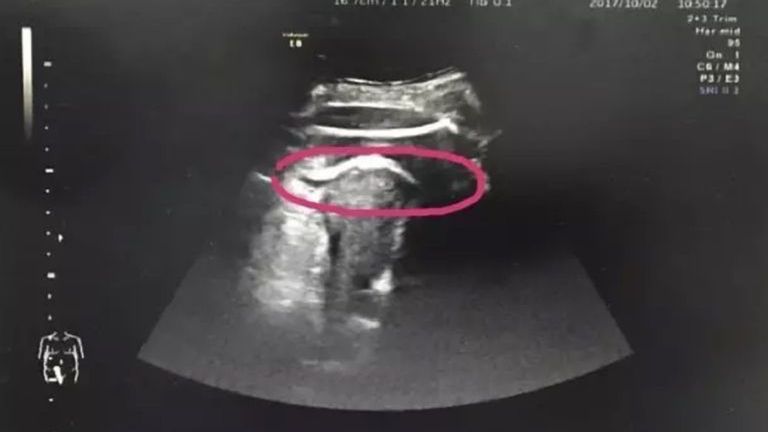

Aby potwierdzić diagnozę, zespół medyczny podjął decyzję o wykonaniu USG. Wszyscy oniemieli, gdy na USG zobaczyli, że dziecko kobiety wystawiło nogę przez dziurę w macicy. W ciągu 5 minut kobieta znalazła się na sali operacyjnej. Zdaniem lekarzy, jej nienarodzona córka tak mocno kopnęła w ścianę macicy, że ta nie wytrzymała i pękła.

(Peking University Shenzhen Hospital) Zdaniem lekarzy nienarodzona wtedy córka tak mocno kopnęła w ścianę macicy, że ta nie wytrzymała i pękła